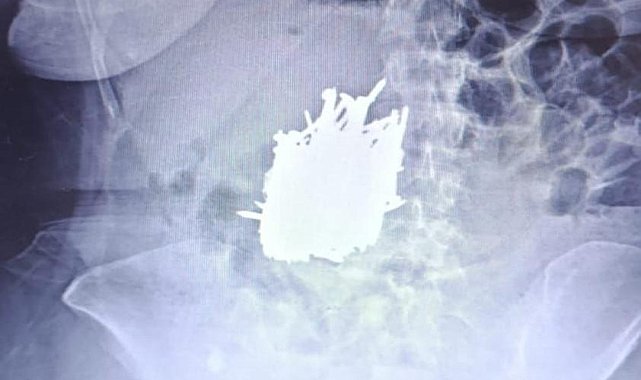

Mersin'in Erdemli ilçesinde karın ağrısı şikayetiyle hastaneye başvuran zihinsel engelli A.K. (52) adlı kadının midesinden yaklaşık 1 kilo çivi, inşaat demiri, kolye, toka gibi çok sayıda metal cisim çıkarıldı. İlçede yaşayan zihinsel engelli A.K., karın ağrısı şikayetiyle Erdemli Devlet Hastanesi'ne başvurdu.

İlçede yaşayan zihinsel engelli A.K., karın ağrısı şikayetiyle Erdemli Devlet Hastanesi'ne başvurdu. Hastaya yapılan tetkik sonucunda kadının midesinde çok sayıda metal cisim olduğu tespit edildi. Hasta, genel cerrahi uzmanı Dr. Can Terzier ve ekibi tarafından acilen ameliyata alındı ve midesinden yaklaşık 1 kilo ağırlığında çivi, inşaat demiri, kolye, toka gibi çok sayıda metal cisim çıkarıldı.